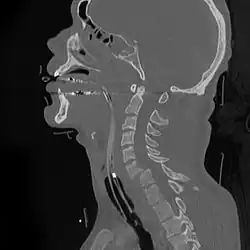

![]() | |

| A fracture of the base of the dens (a part of C2) as seen on CT | |